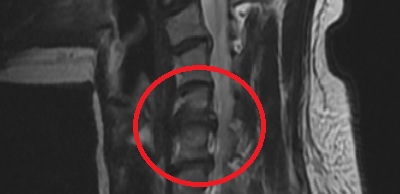

시술하고 난 후 심하게 저림 증상과 두통이 나아졌지만 저림은 계속 있었고 확실한 건 두통은 머리가 맑은 것처럼 사라졌습니다. 3개월 동안 저림이 심해서 시술해준 원장님을 달달 볶을 만큼 너무 아프다고 조르고 조르고 했는데 그때 당시 목에

주사 더 맞으려고 했으나 젊은 나이에 약을 너무 과하게 쓰는 건 안 좋다며 물리치료나 운동치료 또는 마사지등으로 이완요법으로 통증을 가라앉히게 했고 신기하게도 3개월이 된 시점에 통증이 나아졌다는 걸 느꼈습니다.

팔이 떨어질 거 같기도 했다가... 결국 너무 아파서 시술받았고 시술받으려 할 때도 통증이 심해서 자세를 제대로 하지 못할 만큼 목이 돌아가지 않았습니다. 시술은 잘되었고 변함없이 저는 시술하고 또 통증이 심하게 와서 통증주사 2번 맞고 한 달 반 만에 통증이 나아졌습니다.

제가 느낀 바로는 통증에 민감한 사람은 시술하고 나서 3개월 정도 시술 후 나아지는 시간까지는 통증을 느끼는 것 같습니다. 하실 계획이 있으시는 분들은 참고하시길 바랍니다. @